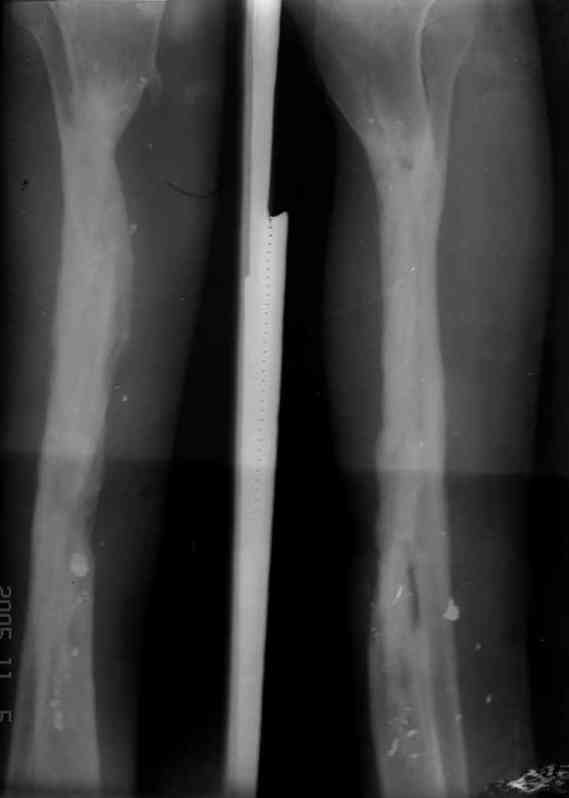

Я думал, что в нижнем отделе голени без мягкотканнего покрытия будет сложно проведения тибиализацию, но твой пример показывает - метод работает даже в таких трудных условиях.

Правда те мои случаи были сделаны давно, еще в Латинской Америке, и конечно качество исполнения отстает от идеалов, но, несмотря на отсутствие нормальных спиц с упором, метод сработал в свое время.

Приходилось встречать замещенные дефекты малоберцовой костью без применения метода Идизарова, и при соблюдении осторожности хрупкая малоберцовая за короткое время под вождействием нагрузки утолщались в диаметре.